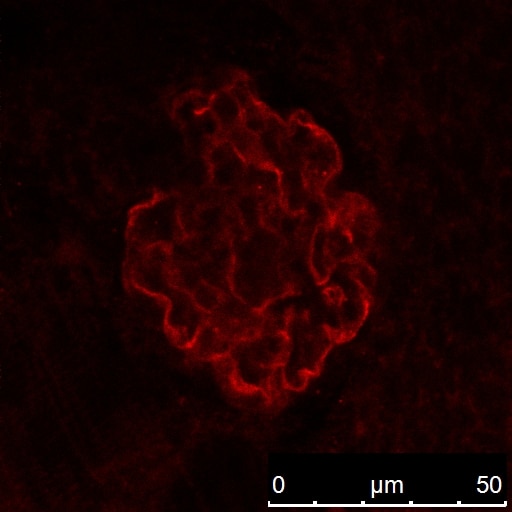

| Positive IF detected in | mouse kidney tissue, zebrafish embryos |

| Immunofluorescence (IF) | IF : 1:300-1:1200 |

NPHS2 (also known as Podocin) is a membrane protein located on the podocyte foot process and is the critical component of the glomerular filtration barrier. Mutations of NPHS2 cause recessive steroidresistant nephrotic syndrome. Two isoforms of NPHS2 exist with molecular weights of 42 kDa and 35 kDa, respectively. (PMID: 21499232)